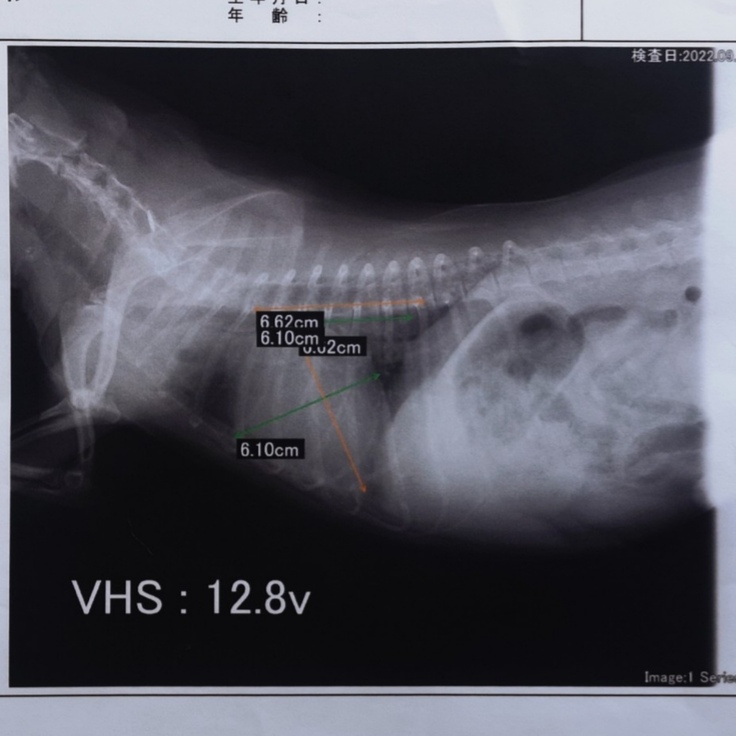

【僧帽弁閉鎖不全症】

この病気にはA~Dまでの五段階のステージがありますが、レオンは二番目に重篤なCです。

犬の心臓僧帽弁閉鎖不全病の手術が出来る施設は全国に数えるほどしかありませんが、その一つが名古屋にあります。

その病院では【僧帽弁形成術】という非常に高度な術式を用います。